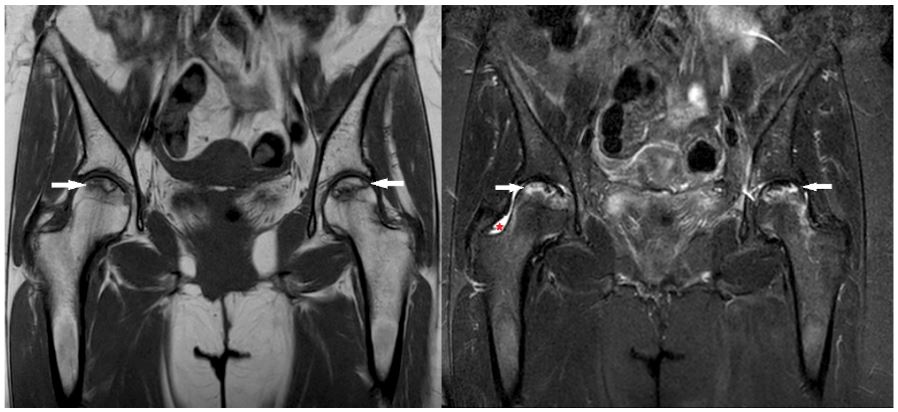

A 47-years-old woman with FIGO stage 3 C1 cervical cancer applied to our clinic in August 2019. She was treated with 50,4 Gy pelvic external beam radiotherapy (EBRT) using the volumetric arc therapy (VMAT) technique with chemotherapy (cisplatin, total 5 cycles of 40 mg/m2 /week). It was followed by 30 Gy intracavitary radiotherapy prescribed to HR-CTV (6 Gy per fraction; once a week). A complete response was achieved three months after. During regular follow-up, 12 months after treatment, the patient complained of pain in her hip and groin. The pain was intensified with movement. In her anamnesis, there was no previous history of trauma or fall. She was a non-smoker, non-diabetic, and non-obese (Body Mass Index: 23.8). She didn’t have any comorbidities. On physical examination, there was a bilateral limitation of motion in hip joints, but there was no visible swelling or redness. Also, the FABER test was positive. The magnetic resonance imaging (MRI) showed a crescent sign and a fissure with bone marrow edema on the bilateral femoral heads (Figure 1). In EBRT treatment plan, only 5% of the bilateral femoral head volume received a dose above 42 Gy. However, the maximum point doses of the right and left femoral heads were found to be 51.3 and 49.4 Gy, respectively. Coronal and axial plan dose distributions of the femur heads are shown in (Figure 2). Considering the patient’s radiotherapy history, imaging findings, and physical examination findings, the patient was diagnosed with bilateral AVN of the femoral head. She was referred to an orthopedic clinic and was advised to undergo bilateral hip arthroplasty. She refused the operation and received conservative NSID and physical therapy. The patient was completely relieved with rest and this regimen. Follow-up MRI at 3- months showed regression of the bone marrow edema on bilateral femoral heads, but the persistence of fissure lines was consistent with AVN. After 1- year, the patient was pain-free and had no difficulty in walking.

Figure 1: Coronal T1 weighted (left) and coronal STIR (Short tau inversion recovery) image (right). A serpiginous area of altered signal intensity is seen in the subcortical area of bilateral femoral heads, showing central marrow signal and ‘double line’ sign (white arrows on left and right). STIR images demonstrates accompanying mild bone marrow edema surrounding the lesions. Note that mild joint effusion is present as well on the right hip (red arrowhead on right). No related sub-chondral collapse or flattening of femoral head is identified. Findings suggest ‘’stage II’’ avascular necrosis of both hips, according to the Ficat-Arlet classification.